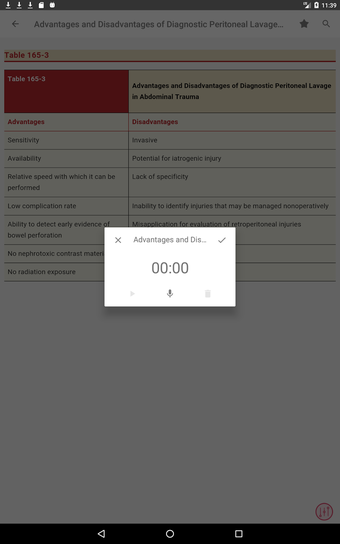

最初に知っておくべきことは、ティンティナリの緊急医療マニュアルが緊急医療の最も重要なトピックについてすべてを提供する包括的なガイドであることです。これは、医師、看護師、および救急医療技師にとって理想的なアプリです。

この無料アプリには、日常の実践に役立つ多くの情報が含まれています。このアプリでカバーされるトピックは、疾患から薬剤、さまざまなタイプの傷害まで幅広く、患者ケアを担当する人々にとって素晴らしいリソースです。